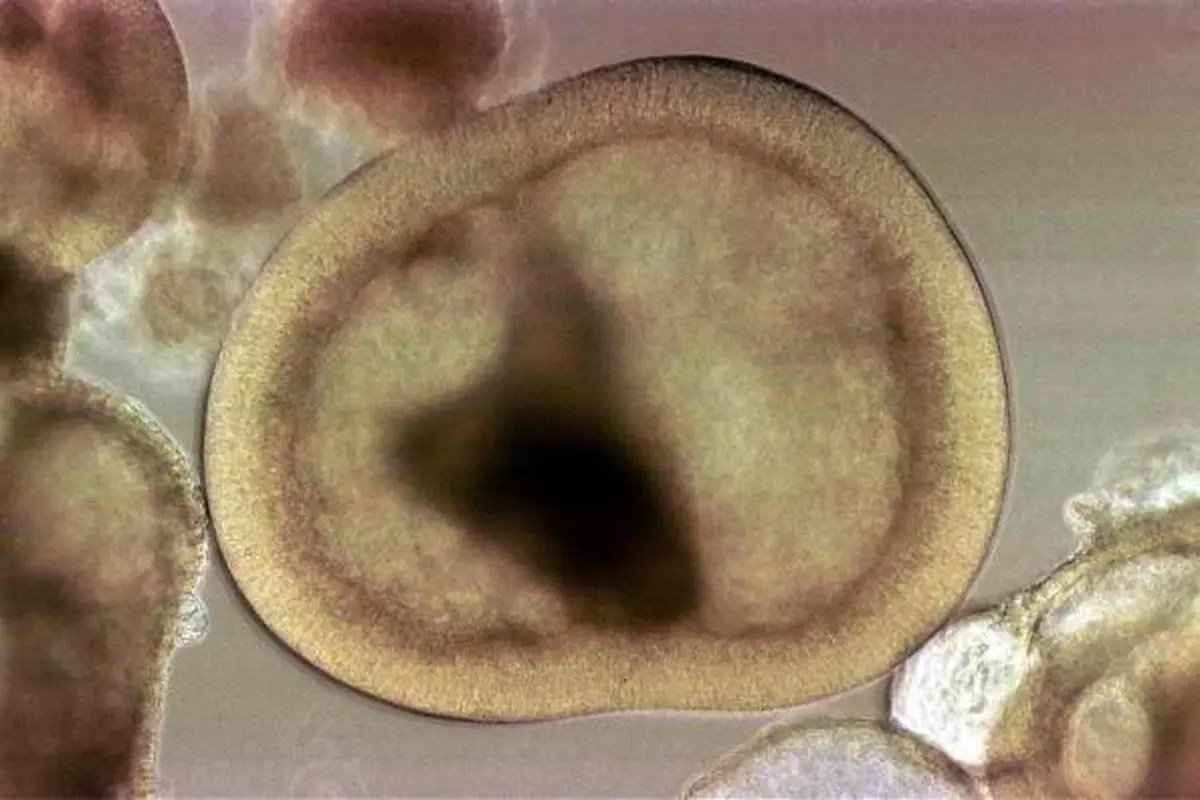

پریوستئوم یا ضریع‌ استخوانی، پرده یا لایه‌ای مانند پارچه است که روی استخوان‌های بدن کشیده شده و به آن چسبیده است. این پرده، غشایی رشته‌ای است که تنۀ استخوان‌های‏ دراز را می‌پوشاند. پریوستئوم از جنس کلاژن است و نقش اساسی در ترمیم استخوان دارد و بدون آن مقاومت استخوان به شدت کاهش می‌یابد.

محققان برای تولید این روکش هوشمند ابتدا با پردازش تصاویر عکس‌های مربوط به پریوستئوم‌ها، ساختار آن را شناسایی کرده و با استفاده از شبیه‌سازی سه‌بعدی موفق شدند نمونه‌های اولیه را تولید کنند.

در زمان ساخت برای شبیه‌سازی هر چه بیشتر این روکش با پریوستئوم که حاوی پروتئین‌های الاستین و کلاژن است، محققان به ترتیب از مواد کشسان و ابریشم استفاده کردند.